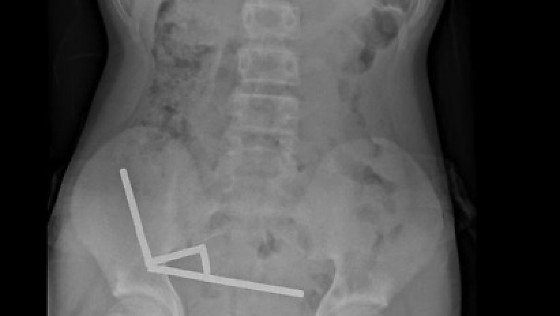

Raio-x abdominal do menino que engoliu entre 80 e 100 ímãs de alta potência

Exames revelaram que os ímãs haviam se agrupado em quatro correntes na parte inferior direita do abdômen, unindo diferentes seções do intestino com sua força magnética, segundo o relatório, que observou que algumas imagens foram distorcidas pelos ímãs. Os médicos então procederam com uma cirurgia exploratória.